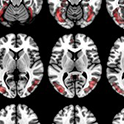

Aphasia is a language problem that often happens after a stroke, but scientists still don’t fully understand why some people have more severe symptoms than others. In this study, we developed and tested a new method called gene-expression lesion-symptom mapping (GLSM).

This study looked at how strokes affect nonverbal cognitive skills, like recognizing patterns and understanding meaning and relationships between things, in people with language disorders after stroke. It focused on whether brain disconnections, especially those caused by white matter hyperintensities (WMH), contribute to these difficulties.

This study demonstrates that AI can accurately measure the integrity of residual brain tissue after a stroke, which has direct implications for neuroplasticity and the severity of language impairments after the stroke (aphasia).

The University of South Carolina is focused on the brain. From autism and aphasia to Alzheimer’s and other related dementias, university researchers are working across several academic disciplines to better understand how the brain works and to develop solutions that will improve people’s health.

As the state’s flagship institution, the University of South Carolina is well has many strengths in both research and treatment of stroke and aphasia — a common consequence of stroke characterized by difficulty speaking or understanding others’ speech. The research is critically important in the state with the seventh-highest incidence of stroke mortality in the U.S.